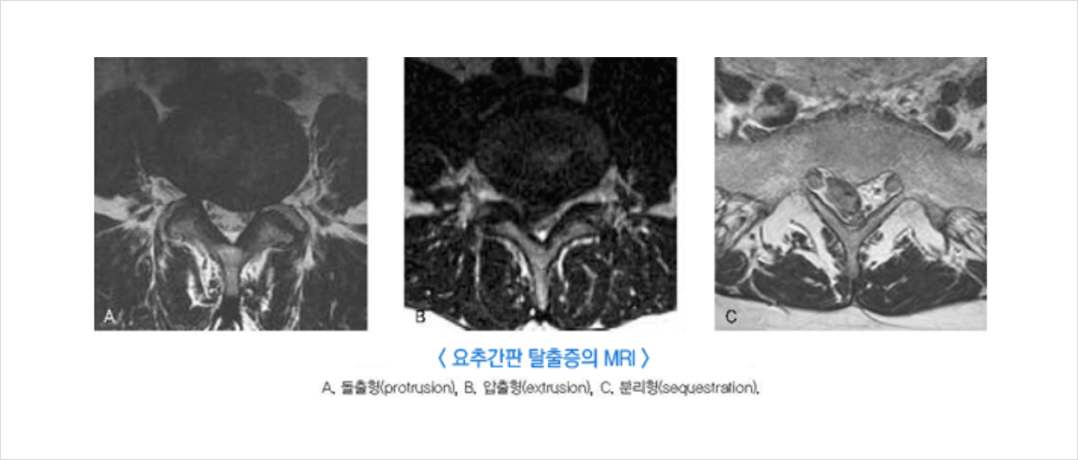

추간판은 크게 두 부분으로 구성되는데, 섬유륜이라 불리는 강력한 외부의 섬유조직과, 수핵이라고 일컫는 젤리 형태의 내부로 구성됩니다.

심한 경우 디스크를 감싼 막이 터지면서 그 안에 있는 수핵이 튀어나옵니다.

이렇게 디스크가 밀려나 주위 신경근을 자극하여 통증을 일으키는 것을 `허리디스크(요추 추간판 탈출증)`이라 합니다.